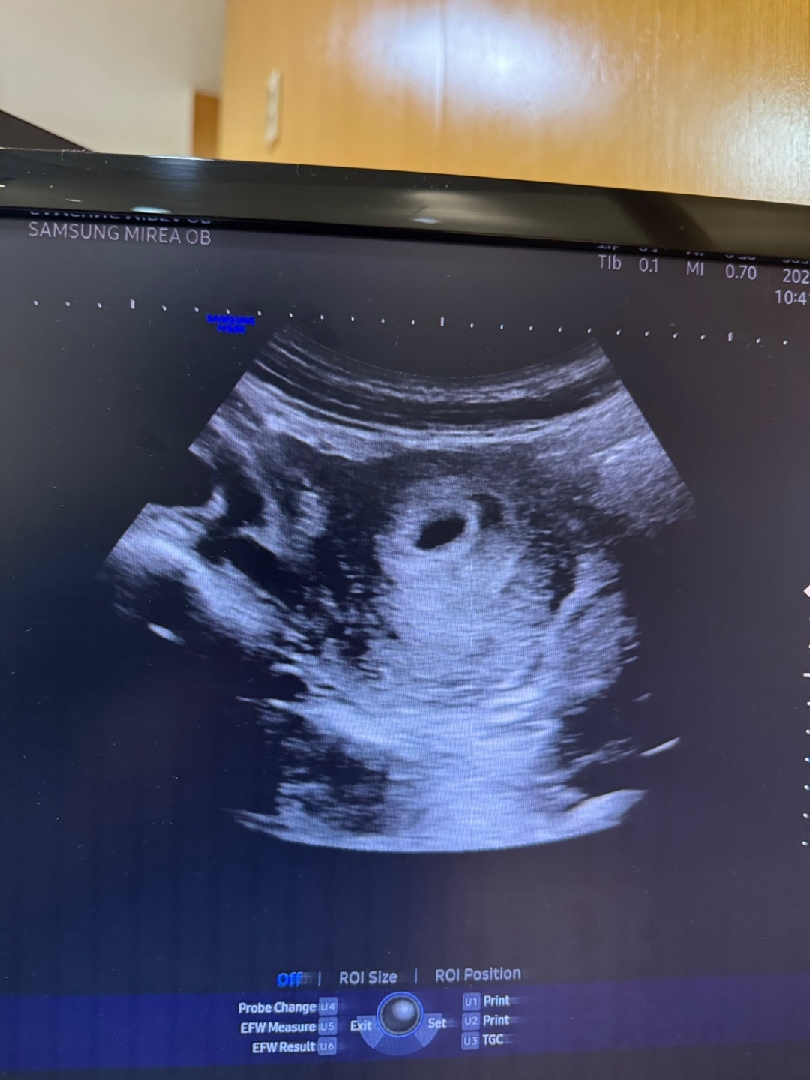

5주3일차 복부초음파

첫 초음파인데 말라서 바로 복부 초음파로 봤어요! 의사쌤은 난황이 보이신다는데 제눈엔 아무리 봐도 안보이는....ㅜㅜㅠ 복부초음파로 봐서 잘 안보이는거 아닌지 괜히 집오니 아쉽네용ㅠㅜㅜㅜ 그래도 잘 자리 잡았다니 다행이에요 다음 볼때까지 시간이 또 얼마나 안갈까요? 4미리 인것도 그냥 신기해요 ㅎㅎ

저도 배로 왔다갔다 봤는데 어느 시점에 하얀 점이 보이더라구요. 그게 난황인데 눈으로만 보고 캡쳐를 안해주셔서 ㅋㅋㅋ 저 장면에선 안보이는거 맞아용

맞아요 예쁜건 캡쳐 안해주시고 심지어 받은 사진은 더 안예뻐요....ㅎㅎ 저것도 그나마 남편이 모니터 찍은사진이에요 ㅎㅎ